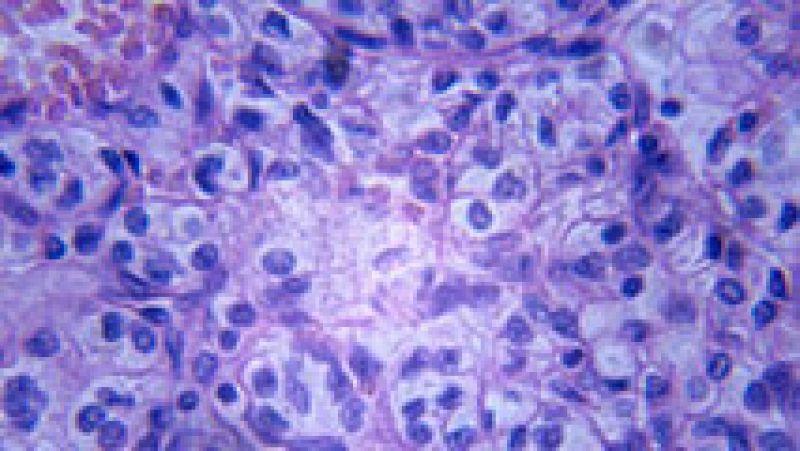

- Se llama Dimate y se utiliza en Francia contra la leucemia

- Ataca a las células malignas conduciéndolas a la apoptosis

- Favorece así la inhibición del crecimiento tumoral